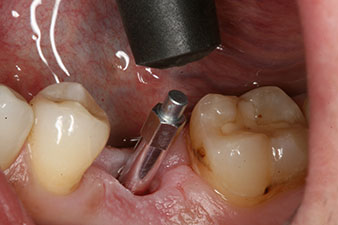

SmartPeg

Fig. 4: SmartPeg measuring posts screwed on to measure the implant stability quotients with the integrated W&H Osstell ISQ module.

The torque used for the machine-driven placement was 43 Ncm. In addition, after screwing a measuring post (SmartPeg) specially matched to the implant, the ISQ value was measured with the probe of the W&H Osstell ISQ module.

This module is an optional extra for the W&H Implantmed and is docked to the implantology motor (see Fig. 11). The dimensionless ISQ value immediately after insertion was 64 orovestibular and 68 mesiodistal (maximum value = 100).